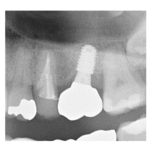

治療途中のインプラント症例

治療途中のインプラント症例です。 主訴 しっかり噛めるようになりたい 年齢 57 ...